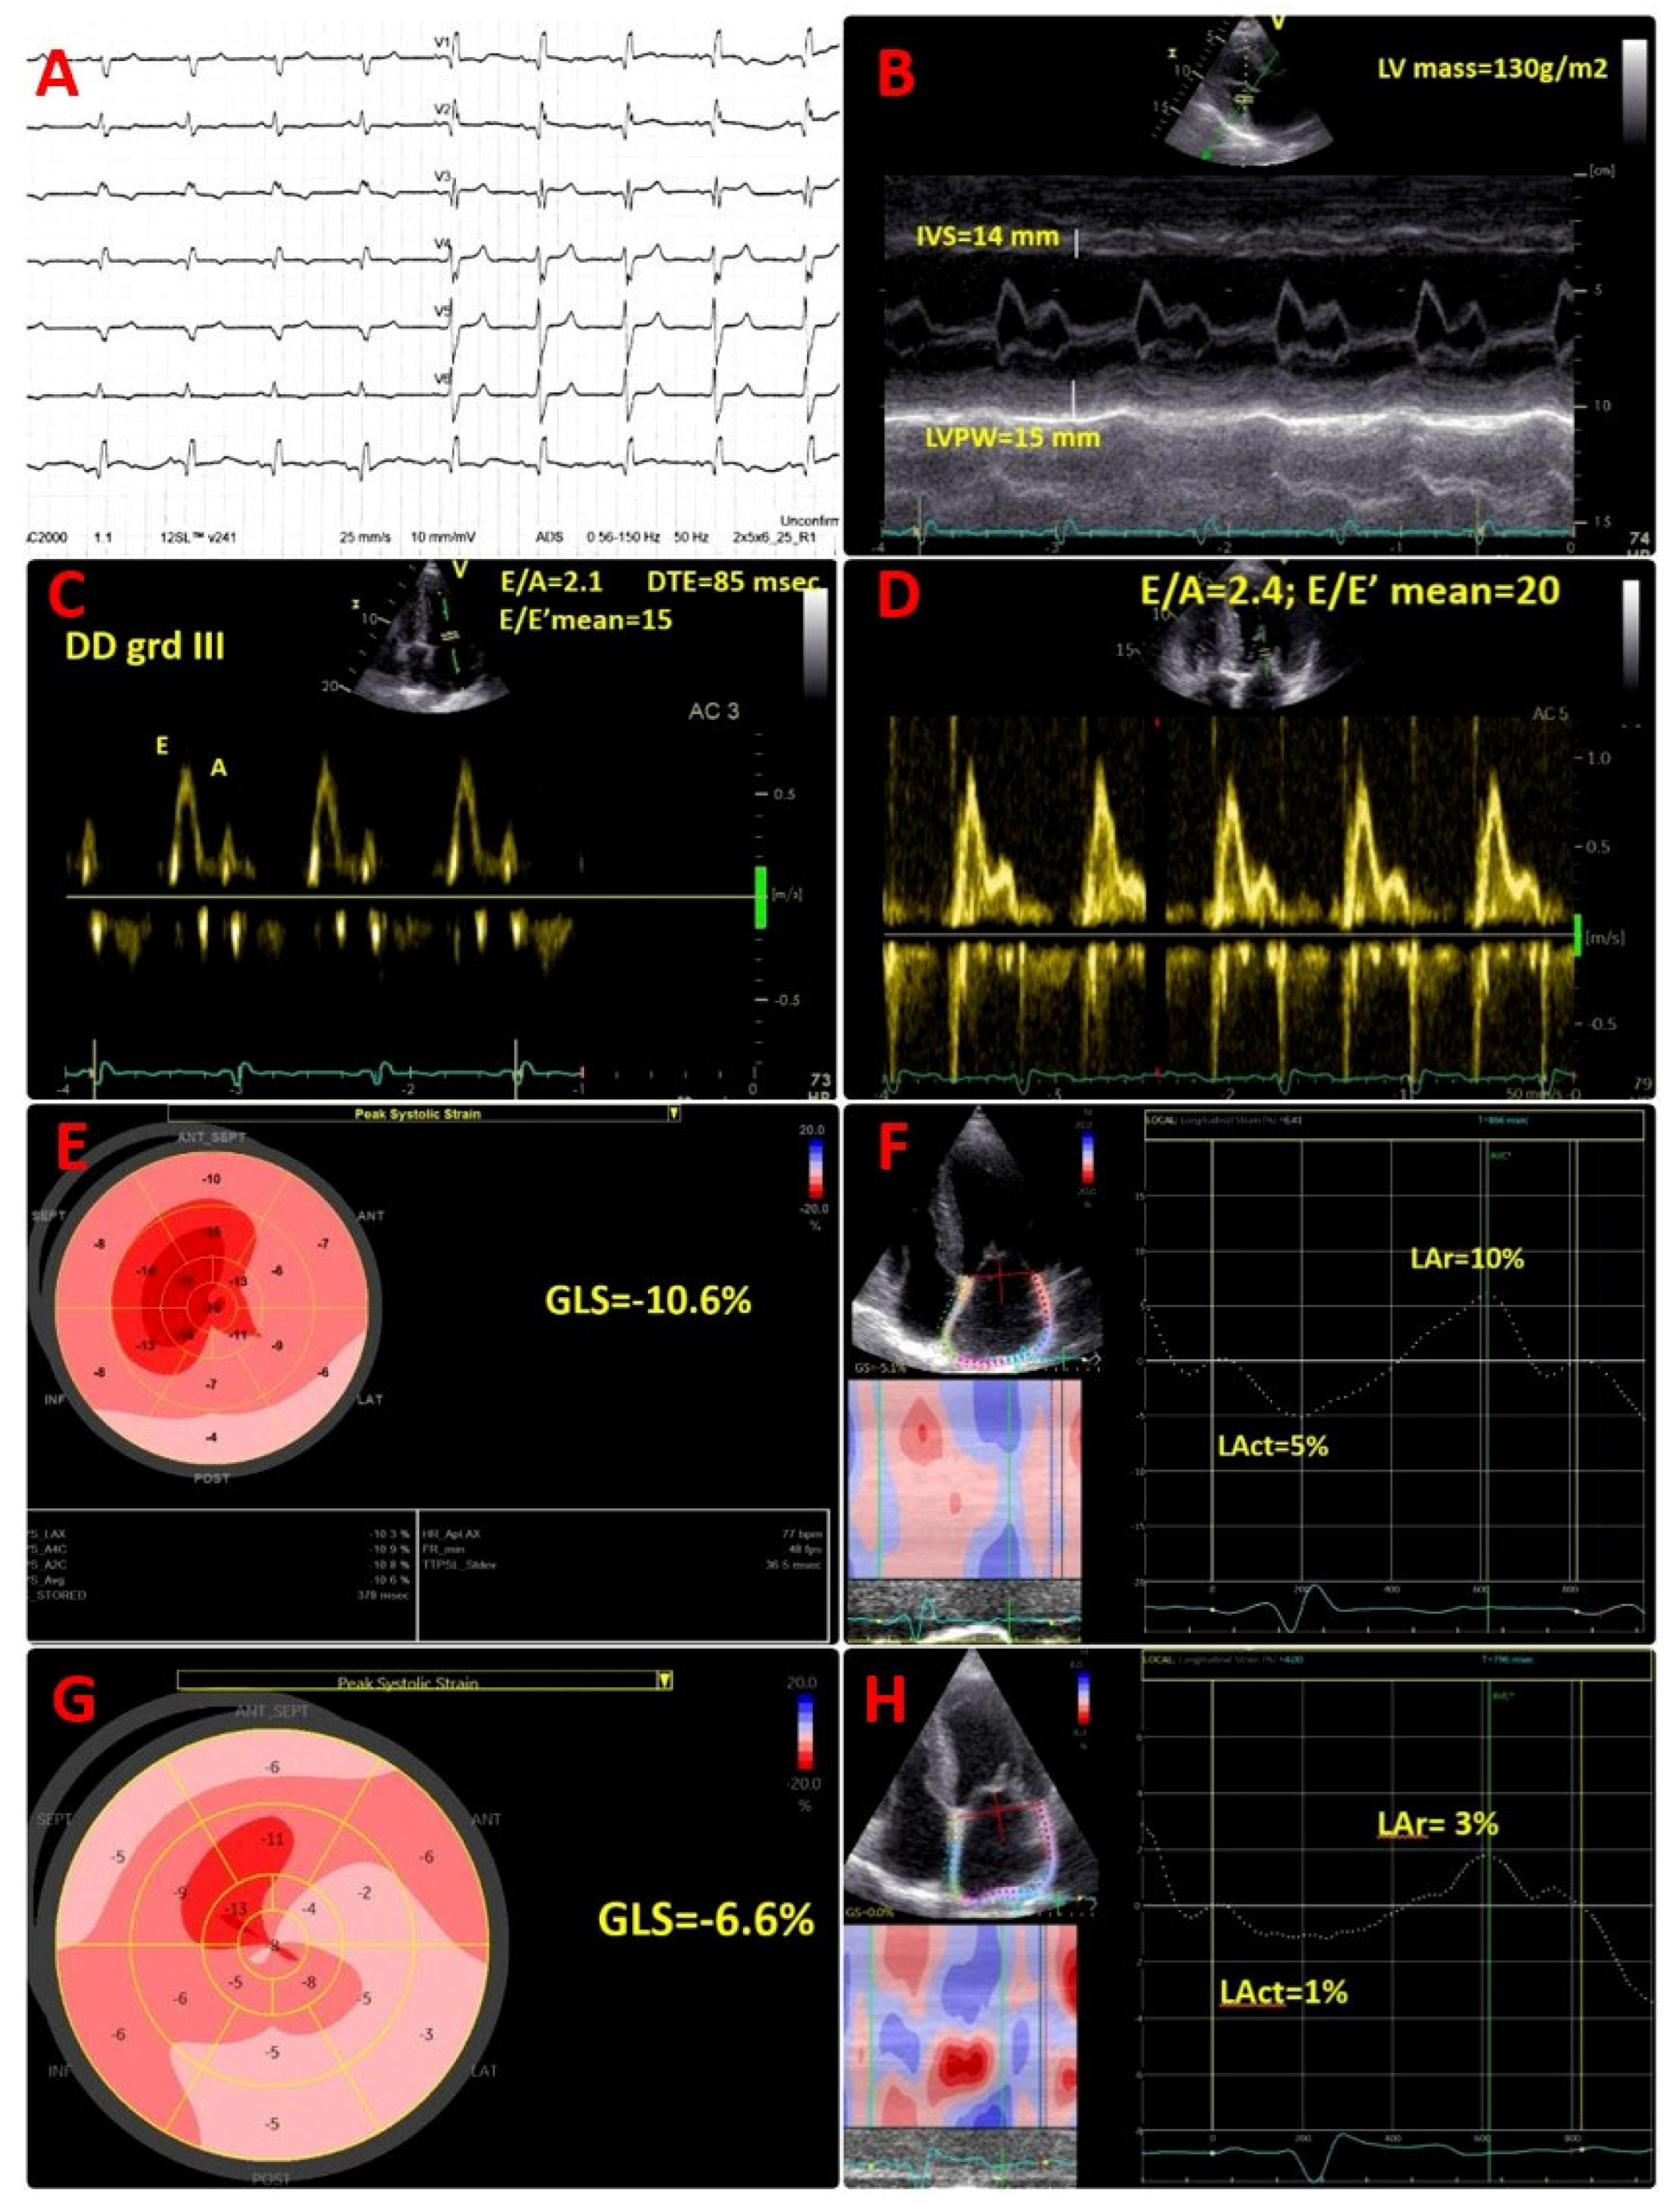

Cardiac troponin I was within the normal range; however, the N-terminal pro B-type natriuretic peptide (NT-proBNP) value was high at 687 pg/mL, in the absence of symptoms. Electrocardiogram (ECG) showed sinus rhythm, right bundle branch block, and pseudo-infarct pattern in V1–V3 (Figure 1A).

Transthoracic echocardiogram (TTE) described a diffuse granular sparkling pattern of the myocardium, with concentric left ventricular (LV) hypertrophy (interventricular septum of 14 mm, LV posterior wall of 15 mm, LV mass of 130 g/m2) and preserved LV ejection fraction (LVEF) of 52% (Figure 1B; Movie S1 in the Supplementary Material). Diastolic function assessment revealed restrictive pattern (grade III diastolic dysfunction), with E/A of 2.1, DTE of 85 msec, E/E′ mean of 15, low tissue Doppler LV myocardial velocities (septal E′ of 5 cm/s, lateral E′ of 9 cm/s), and severe left atrial enlargement (LAVi = 62 mL/m2) (Figure 1C). Of note, an abnormal global longitudinal strain (GLS = −10.6%), with apical sparring pattern was present (Figure 1E), associated with severely impaired left atrial reservoir and conduit strain (LAr = 10%, Lact = 5%) (Figure 1F). Moreover, TTE showed moderate tricuspid regurgitation, normal systolic pulmonary artery pressure (sPAP) = 25 mmHg, infiltrated thickened right ventricular (RV) free wall of 8 mm, reduced tricuspid plane systolic excursion (TAPSE) of 16 mm, and reduced longitudinal myocardial velocity (S’ of 8 cm/s).

He presented with dyspnoea on moderate exertion and fatigue, NYHA class II, bilateral leg oedema with significantly increased NT-proBNP value of 3368 pg/mL. Echocardiographic assessment showed deterioration of LV systolic function, with reduced LVEF (39%) and decreased GLS (−6.6%), and worsening of diastolic function parameters: mean E/E′ ratio of 20, lower tissue Doppler LV diastolic myocardial velocities (septal E′ of 4 cm/s, lateral E′ of 5 cm/s). An additional decline of LA reservoir and conduit strain (LAr = 3%, Lact = 1%) (Figure 1D,G,H) was found, suggestive for progressive atrial myopathy. A similar progression of RV dysfunction was detected, with decreased TAPSE of 14 mm. ECG monitoring (24 h) did not show any arrhythmias. Transoesophageal echocardiography showed no thrombus.

Figure 1. ECG and transthoracic echocardiographic images. (A) ECG- sinus rhythm, right bundle branch block, and pseudo-infarct pattern in V1–V3; (B) concentric left ventricular (LV) hypertrophy (IVS, interventricular septum of 14 mm, LVPW, LV posterior wall of 15 mm, LV mass of 130 g/m2); (C) restrictive filling pattern, with E/A of 2.1, DTE of 85 msec, E/E′ mean of 15, E = peak of early filling velocity, A = peak of late atrial filling velocity, DTE = mitral flow deceleration time, E′ = early diastolic tissue velocity; (D) worsening of diastolic dysfunction, restrictive filling pattern, with E/A of 2.4, E/E′ mean of 20; (E) bull’s eye plot by 2D speckle tracking echocardiography (STE) with significantly reduced global longitudinal strain (GLS) (−10.6%) and global altered deformation mainly at the basal and mid-ventricular segments, with a typical “apical sparing” pattern; (F) 2D STE at the level of the left atrium (LA) showing significantly decreased LA contractile function (Lact) and also of LA reservoir function (LAr); (G) bull’s eye plot by 2D speckle tracking echocardiography (STE) with additional significant reduction in global longitudinal strain (GLS) (−6.6%) and global altered deformation mainly at the basal and mid-ventricular segments, with a typical “apical sparing” pattern; (H) 2D STE at the level of the left atrium (LA) showing additional significantly reduction in LA contractile function (Lact = 1%) and also in LA reservoir function (Lar = 3%).